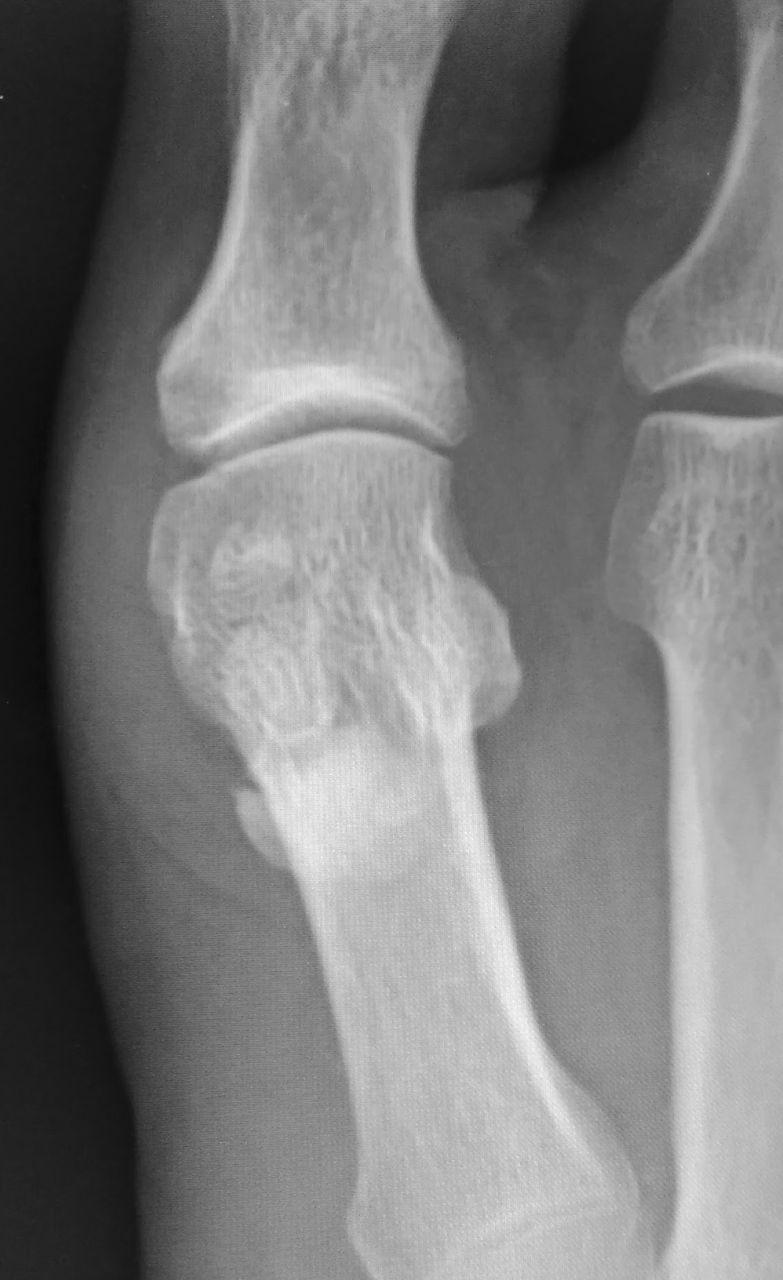

何の疑いもなく「痛風ですね」と言いそうになって、単純X線像を見てハッと息を飲みました。それが下の画像です。

正面像で2つの種子骨の下に何かクルミのような像を認めます。ただ、正面像では正直に言って見逃しかけました。

しかし、斜位像では、種子骨よりも中枢側にはっきりとした石灰沈着象を認めます。これは、痛風ではないかもしれない・・・。

足部の側面像を撮影して、確定診断にいたりました。長母趾屈筋腱に発生した石灰沈着性腱炎です。う~ん、痛風発作と非常に紛らわしい。

しかし、これを誤診してしまうと、長期間に渡る高尿酸血症の治療を開始してしまう危険性があります。たまたま気付いてラッキーでした。。。